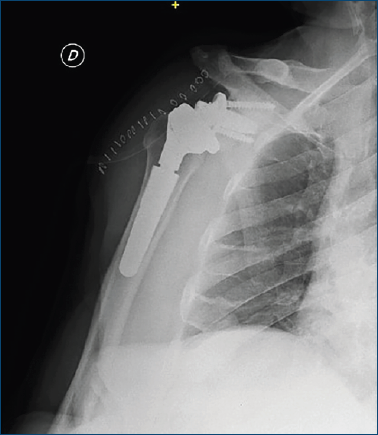

Circa 14 mesi dopo la revisione, il paziente si è presentato a una visita di follow-up dopo aver subito un trauma alla spalla. Le radiografie hanno evidenziato la mobilizzazione della glenosfera, e la TC preoperatoria ha confermato la diagnosi (Fig. 2), rendendo necessaria un’ulteriore revisione chirurgica.

Figura 2. TC della spalla destra, coronale. La glenosfera è visibile e risulta dislocata superiormente e anteriormente.